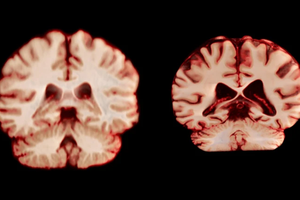

12月4日,胡志明市卫生厅表示,本市手足口病例正在大幅增加,尤其是 EV71 病毒株的卷土重来。这种病毒株可能导致重症并发症,加剧疫情爆发风险。